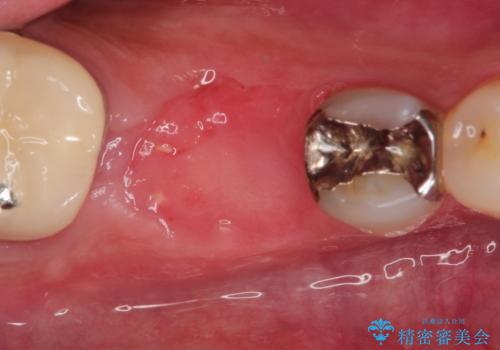

抜歯をしたあと骨が痩せないよう抜歯直後に骨補填材を入れています。

骨が成熟するまで待ち、インプラントを埋入しました。